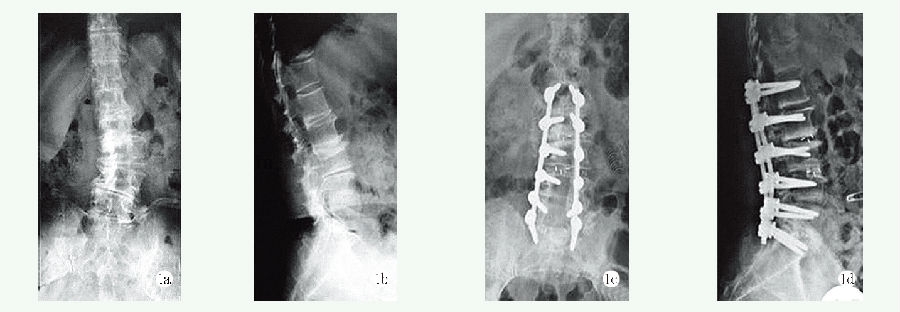

两组影像测量结果见表4,与术前相比,末次随访时两组患者侧弯Cobb 角、C7PL 和SVA 均显著减少(P<0.05)。术前两组间侧弯Cobb 角、C7PL 和SVA 的差异均无统计学意义(P>0.05),末次随访时,长节段组的侧弯Cobb 角、C7PL 和SVA 均显著小于短节段组(P<0.05)。典型影像见图1、2。

图1 患者,女,64 岁,主诉腰部疼痛及麻木,确诊为DS,接受长节段减压融合治疗

1a, 1b: 术前X 线片显示腰椎侧凸  1c, 1d: 术后X 线片提示侧凸Cobb 角获得明显改善